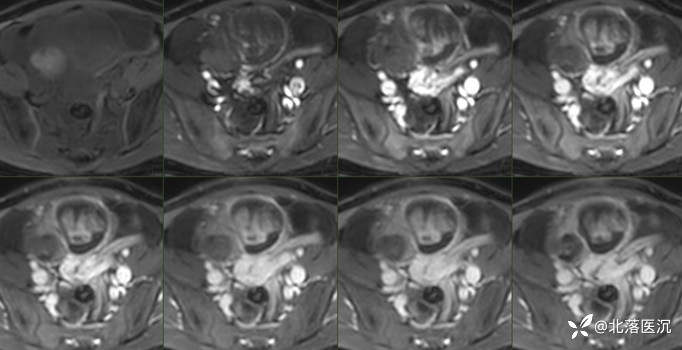

影像学表现:

双侧附件区可见巨大囊性包块影,最大截面大小约203X119mm,98x95mm,囊液密度均匀,未见明显分隔,病变左侧可见斑片状脂肪密度影及结节状钙化影,边界清楚,下方小病变内见脂液平面,周围肠管及子宫受压移位。腹膜后主动脉旁及升结肠周围脂肪间隙内见多发肿大淋巴结,较大者短径约10mm。

脾脏体积增大,下缘达肝缘下,实质内未见明显异常密度影;其余脏器未见明显异常。

影像学诊断:

1、双侧附件区占位,考虑囊性畸胎瘤可能,畸胎瘤继发浆液性囊腺瘤待除外,建议MRI增强检查;

2、脾大,请结合临床。